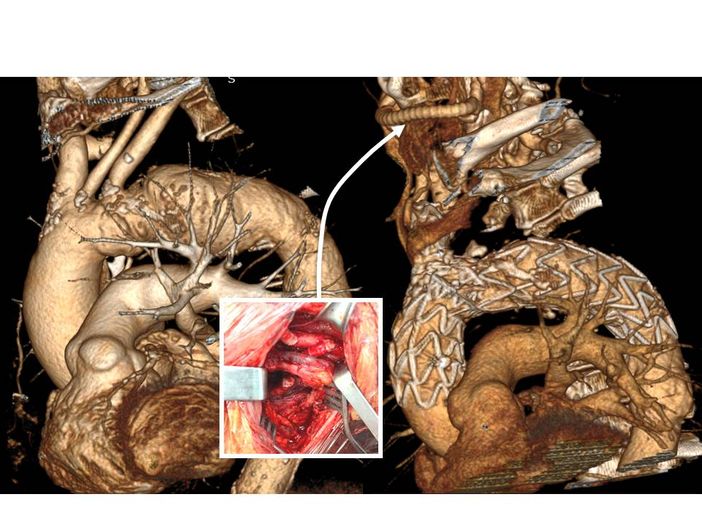

L’intervento, eseguito in emergenza dall’equipe della Cardiochirurgia, diretta dal Dott. Andrea Musazzi, ha permesso di salvare la vita della paziente. Nelle settimane seguenti, tuttavia, per la recidiva di dolore toracico, è stata identificata a mezzo di un’angio-TC la progressione della pregressa malattia verso una vera e propria lesione dissecativa dell’arco aortico, un segmento la cui eventuale gestione operatoria è difficile e complessa per le caratteristiche anatomiche ed emodinamiche di quel segmento, curvilineo e da cui originano strutture vitali come i tronchi sovra-aortici per irrorano il cervello e il cervelletto.

“La sede anatomica delle lesioni trattate richiede il posizionamento di questa speciale endoprotesi molto vicina alle strutture nobili cardiache - spiega il Prof. Gabriele Piffaretti - In questi casi, ed in particolare con questo tipo di endoprotesi, prima di procedere all'intervento vero e proprio si è reso necessario impiantare, ad opera dei cardiologi interventisti, un pace-maker temporaneo.” I pazienti sono stati quindi portati in sala operatoria, dove i chirurghi vascolari hanno eseguito due bypass cervicali per mantenere costante l’irrorazione cerebrale anche dopo il posizionamento della protesi nell'aorta.

Solo a quel punto, insieme ai radiologi interventisti, si è potuti passare ad inserire per via endovascolare la protesi ramificata nel tratto dell'aorta ascendente e dell'arco, un segmento in cui è massima la pressione esercitata dal sangue in uscita dal cuore e le cui pareti si dilatano e si contraggono in sintonia con il ritmo cardiaco.

"Queste protesi sono state studiate per adattarsi al meglio anatomicamente alle sollecitazioni emodinamiche così vigorose in questo primo tratto di aorta toracica’ – continua Piffaretti – Per ridurre tali interferenze indotte dal battito cardiaco e dalla spinta pressoria, e quindi per ottimizzare il posizionamento dell’endoprotesi limitando il rischio di interferire con l’origine delle arterie coronarie o ledere la valvola aortica, è necessario che l’impianto eseguito a quattro mani dal chirurgo vascolare e dal radiologo interventista sia accompagnato in quella fase delicatissima da una fibrillazione cardiaca indotta e regolata dal cardiologo tramite il pace-maker temporaneo".